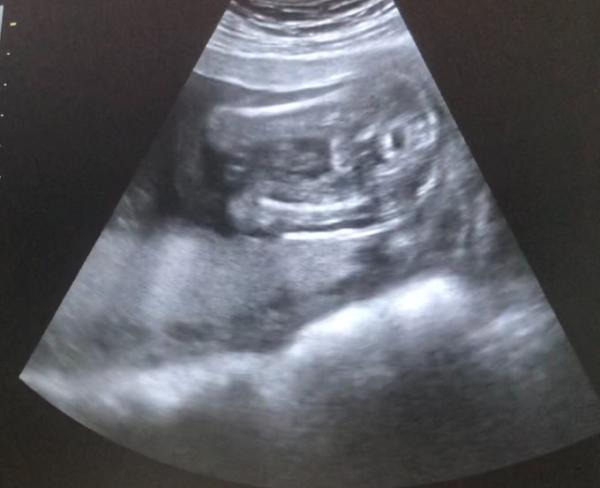

Hallo, ich bin in der 21. SSW und es wird mein erstes Kind. Ich war gestern beim Frauenarzt und es lief soweit alles gut. Als meine Frauenärztin dann das Geschlecht sagen wollte, war sie sich total unsicher. Bei dem Termin vor 1-2 Monaten tippte sie auf Junge, gestern meinte sie es könnte doch ein Mädchen sein. Jetzt bin ich total unsicher und aufgeregt, weil ich natürlich wissen möchte was es wird :-) Kann man von dem Screenshot irgendwie erkennen was es wird? Vielen Dank schonmal für die Antwort. Ganz liebe Grüße Yasemin

Bild zu Geschlecht unklar - Help - Schwanger - wer noch? Rund um die Schwangerschaft

Hallo, könnte tatsächlich ein Mädchen oder ein Junge sein, man sieht es schlecht. Aber ich denke ein Junge, ist mir nämlich etwas zu kugelig für ein Mädchen. Liebe Grüße

Ich finde das sieht aus wie ein Junge, sieht für mich auch zu rund/kugelig aus. Aber meine Tendenz ist eher so 60/40 also Mädchen nicht auszuschließen. Noch ein bisschen abwarten und geduld zeigen. Meine hat sich bis zum bitteren Ende nicht gezeigt LG. Asude

Hallo ich würde eher vermuten ein Mädchen, man sieht schon 3 Striche . Wenn es ein Junge wäre in dieser ssw schon deutlich erkennbar .

Hallo Yasemin, für mich sieht das bissle aus wie Hoden, diese runden Bälle :-)) aber keine Ahnung. Es bleibt spannend. Bei meinem ersten Kind hat die Ärztin mir bereits in der 13. Woche gesagt was es wird. Nämlich ein Bub. Bei Jungs sieht man es meistens schneller, weil der Pipi oft iwo zu erkennen ist. Aber bei dieser SS hat es bis zu 26. Woche gedauert, weil der Kleine immer blöd lag. Hauptsache gesund und munter :-)) hayrls olsun :-)

Tippe auf Junge. Das sieht komplett anders aus als der Ultraschall meiner Tochter in der 20. SSW. Das Geschlecht sah aus wie eine Kaffeebohne. Aber auf deinem Bild sieht es eher aus wie kleine Kugeln. Daher vermute ich, es sind Hoden.